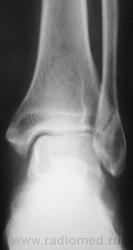

Травма. Пациент направлен на рентгенографию голеностопного сустава.

напоминает перелом по типу Фолькмановского клина.

Фолькмана перелом (f. Volkmann) - разновидностью перелома Дюпюитрена, отличается тем, что наряду с переломом медиальной лодыжки и малоберцовой кости происходит перелом латерального края дистального эпиметафиза большеберцовой кости, отломок которого обычно имеет треугольную форму. Впервые описан Volkmann R.

(то есть при трехлодыжечном переломе).

А какова давность травмы? Уж слишком четкие края у этой "линии перелома". Но она почему то не пересекает кортикальную пластинку наружней лодыжки.